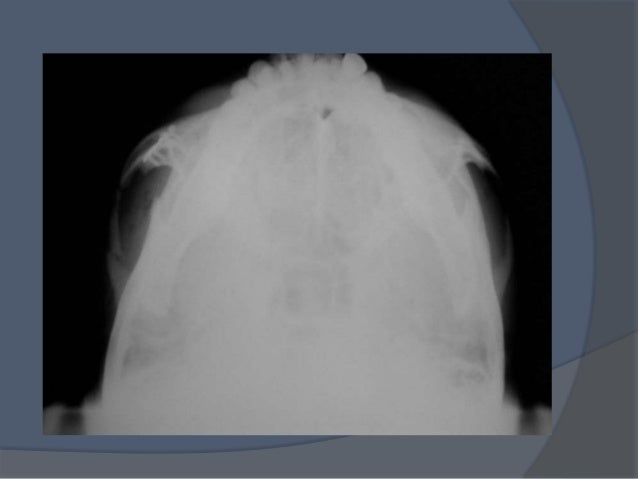

El arco cigomático es una parte del cráneo humano, más concretamente de la cara humana. El arco cigomático se forma en la unión de la apófisis cigomática del hueso temporal propio de los huesos del cráneo y la articulación del apófisis malar, propio de los huesos de la cara, ubicado a un lado de las fosas orbitales.[1]